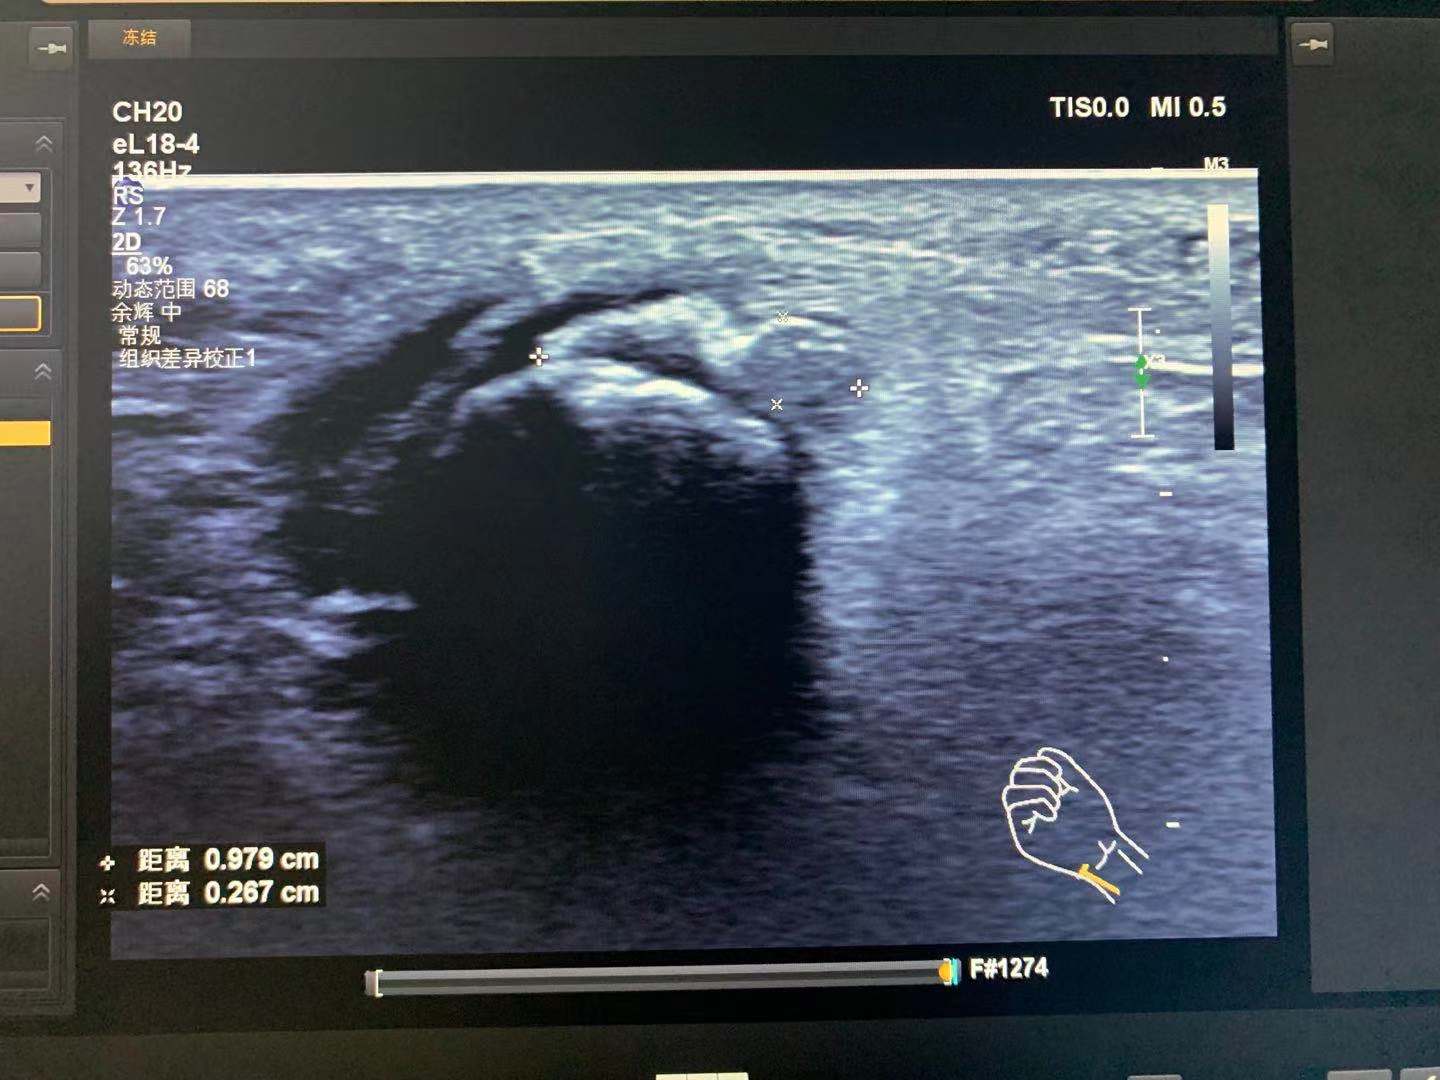

_20210804215142 - Bird Ultrasound

_20210804215142

Xue Heng

05/08/2021